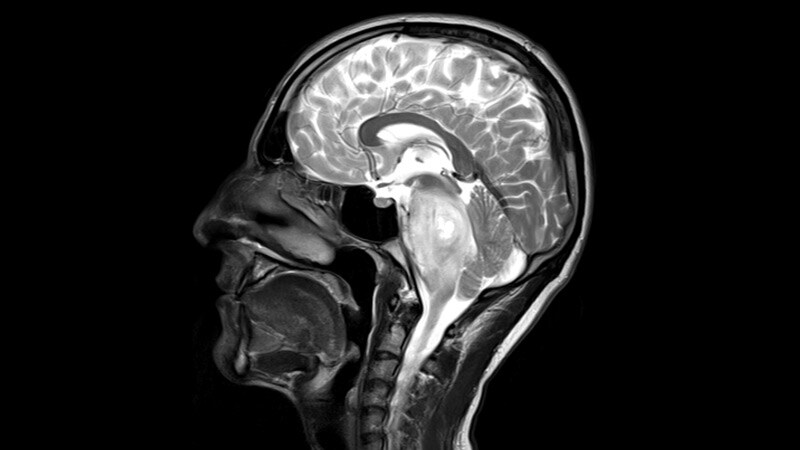

Brain Cancer

Biodegradable Brain Implant Delivers Life-Saving Cancer Meds